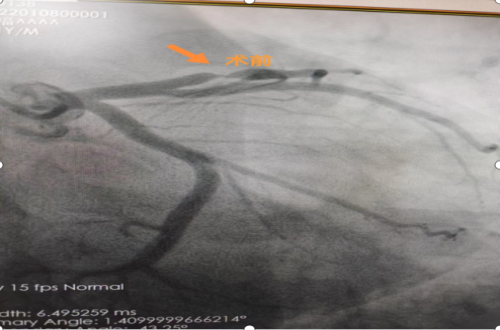

支架植入术后